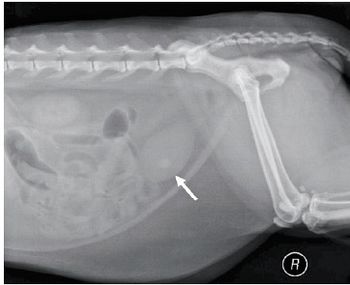

The most common presentation of salivary mucoceles in cats isn't cervical swelling.